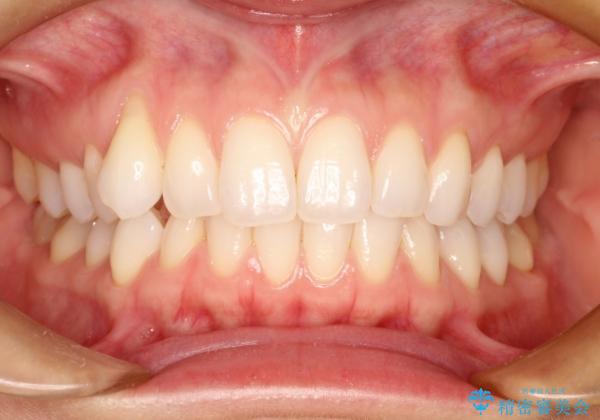

右上の八重歯を気にされてご来院されました。結婚式を控えていたため挙式にまでに可能な限りキレイにしたいとのことでした。

また、ホワイトニングも一緒にご希望されたため、挙式のタイミングに合わせてレーザーホワイトニングを施術させていただきました。

右上の犬歯の歯茎は矯正前から退縮を起こしていましたが、矯正後もその退縮に関しては変化がありませんでした。今回は患者様が歯肉退縮に関しては治療をご希望ではありませんでしたが、当院ではこのように歯茎が下がり露出した根面を、歯茎を移植することでカバーし見た目を改善する手術を行っています。